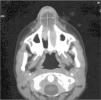

El hematoma septal tras traumatismo nasal es una complicación que de no ser diagnosticada y tratada precozmente puede evolucionar a un absceso septal. Presentamos el caso de un varón de 10 años que sufrió traumatismo nasal con fractura de huesos propios y un hematoma septal que no fue diagnosticado, y cuya evolución fue un absceso septal. Durante el drenaje de este absceso se evidenció una necrosis del cartílago cuadrangular. Posteriormente el paciente presentó un hundimiento del dorso nasal y una desviación del tabique nasal. Esta secuela se corrigió mediante la utilización de un injerto osteocondral costal. Ante cualquier traumatismo nasal es importante explorar correctamente el tabique nasal para descartar un hematoma, que si no se drena de forma precoz, puede evolucionar a un absceso por compresión del cartílago cuadrangular, cuyas consecuencias son su necrosis en pocos días y posterior hundimiento del dorso nasal en el curso del desarrollo del niño.

Septal haematoma following nasal trauma is a complication that, if not diagnosed and treated early, may evolve into a nasal septal abscess. We present the case of a 10-year-old male who suffered nasal trauma with fracture and an undiagnosed septal haematoma that evolved into a septal abscess. During drainage of the abscess, necrosis of the quadrangular cartilage was noted. The patient later presented collapse of the nasal dorsum and deviation of the nasal septum. This sequela was corrected by means of an osteochondral costal graft. In the presence of any nasal trauma, it is important to explore the nasal septum correctly to discard the presence of a haematoma which, if not drained early, may evolve into an abscess due to compression of the quadrangular cartilage, leading to its necrosis in a few days and later collapse of the nasal dorsum as the child grows.